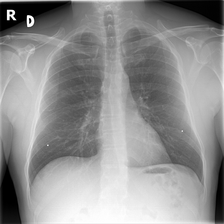

To assess whether dataset-specific signals are present in images independent of pathology, we train a 4-way classifier to predict dataset source (MIMIC-CXR, CheXpert, ChestX-ray14, PadChest). We use DenseNet-161, which achieved the highest internal AUROC and AUPRC in three of the four datasets in our domain shift analysis. Using the strongest-performing architecture ensures that any ability to distinguish dataset sources reflects genuine learnable signatures rather than limitations of model capacity. This DenseNet-161 backbone is trained from scratch on our four training datasets, using only pixel data. Performance is evaluated using Sensitivity, Specificity and F1-Score for each of the four classes (source datasets). As chance-level accuracy is 25%, substantially higher performance would indicate that non-pathological features (e.g., text markers, intensity scaling, acquisition artefacts) allow models to distinguish datasets. Results are shown in Table 5. Example images from each source dataset are shown in Figure 5.

The DenseNet-161 dataset-source classifier achieved near-perfect performance across all four classes (source datasets), far exceeding the 25% chance level. This indicates that public chest radiography datasets contain strong, easily learnable site-specific signatures. which are deeply embedded in the data. These signals are unrelated to pathology and instead likely reflect differences in acquisition protocols, scanner hardware, image post-processing pipelines, or embedded text markers. This finding highlights a critical shortcoming of current public benchmarks - models may exploit non-clinical cues that distinguish datasets rather than learning generalisable representations of disease.

Refer to caption

(a) CheXpert

(b) MIMIC-CXR

(c) ChestX-ray14

(d) PadChest

(e) CheXpert

(f) MIMIC-CXR

(g) ChestX-ray14

(h) PadChest

Figure 5: Example chest radiographs from MIMIC-CXR, CheXpert, ChestX-ray14 and PadChest. Each image contains text artefacts.